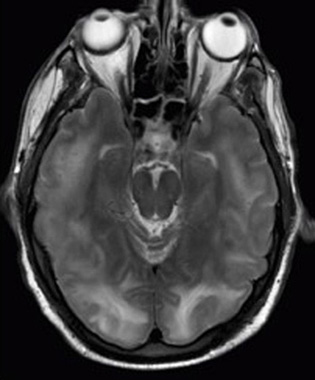

Physics has many applications in the biological sciences. On the microscopic level, it helps describe the properties of cell walls and cell membranes (Figure 5 and Figure 6). On the macroscopic level, it can explain the heat, work, and power associated with the human body. Physics is involved in medical diagnostics, such as x-rays, magnetic resonance imaging (MRI), and ultrasonic blood flow measurements. Medical therapy sometimes directly involves physics; for example, cancer radiotherapy uses ionizing radiation. Physics can also explain sensory phenomena, such as how musical instruments make sound, how the eye detects color, and how lasers can transmit information.